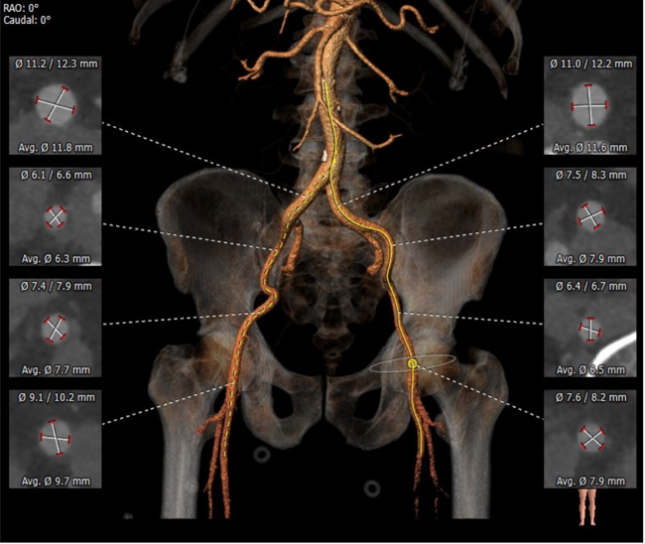

右侧髂外动脉轻度扭曲,双侧股髂动脉血管直径良好

外周血管及主动脉弓解剖

③患者双侧入路血管条件佳,常规选择右侧股动脉为主入路,左侧为辅入路。